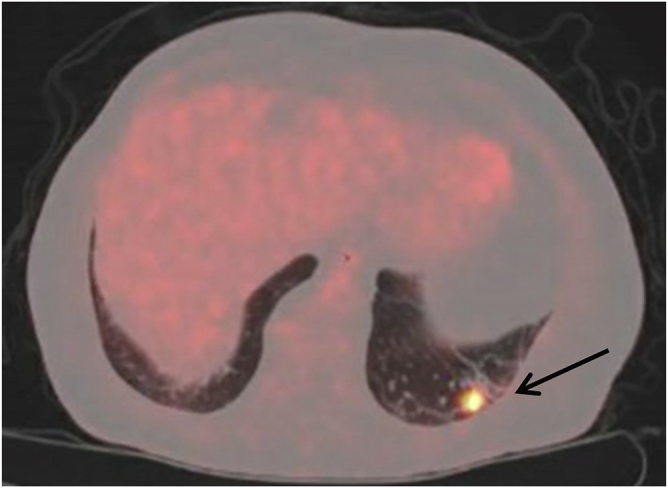

Prescottella (Rhodococcus) soli is a soil-dwelling organism not previously thought to be pathogenic in humans. We discuss the case of a 78-year-old male renal transplant recipient presenting with respiratory symptoms and multiple pulmonary nodules, found to be pulmonary malakoplakia secondary to infection with Prescottella (Rhodococcus) soli. Treatment was commenced with vancomycin, meropenem and azithromycin for an induction period of two weeks and continued with indefinite oral moxifloxacin and azithromycin with significant clinical improvement. Although rare, Prescottella species, including Prescottella soli, should be considered in the differential diagnosis of pulmonary nodules, particularly in immunocompromised patients. More data is required to inform optimal treatment.